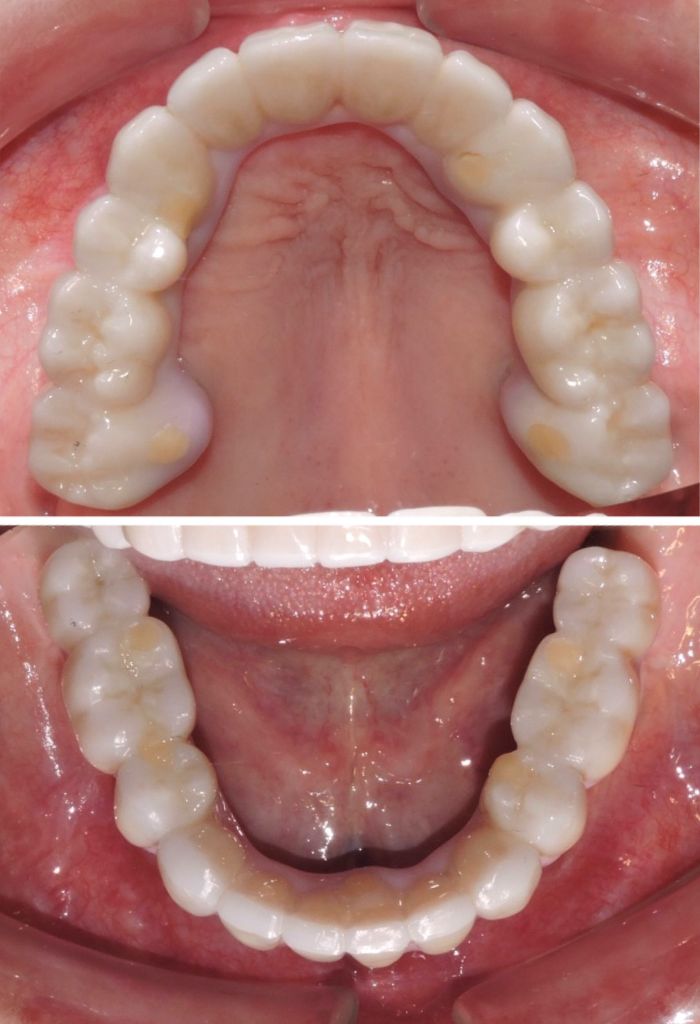

Before

After